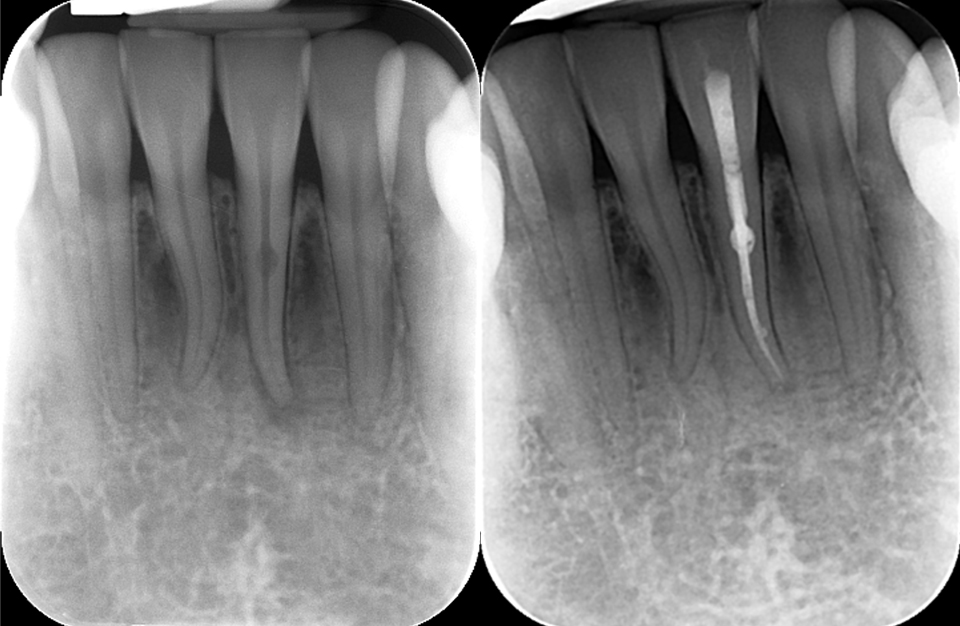

- Root canal treatment is designed to clean out the infected or damaged pulp tissue, thoroughly disinfect the area, and replace it with a durable, inert material called gutta-percha. This helps restore the tooth’s structure and function while also preventing further infection, thus allowing the tooth to be saved.

Cone-Beam CT (CBCT)

- For more complex cases, you may be referred for a Cone-Beam Computed Tomography (CBCT) scan, a 3D imaging technology that provides highly detailed scans of your tooth. The CBCT scan allows Dr Bose to visualise the tooth, its roots, and surrounding structures in three dimensions, offering a much clearer understanding of the tooth’s anatomy and any potential issues.

- This advanced imaging is particularly helpful when treating challenging cases, such as teeth with curved or calcified root canals, or when the anatomy is difficult to discern with traditional X-rays. CBCT can assist in precise diagnosis and treatment planning, ensuring that the procedure is as effective and efficient as possible.